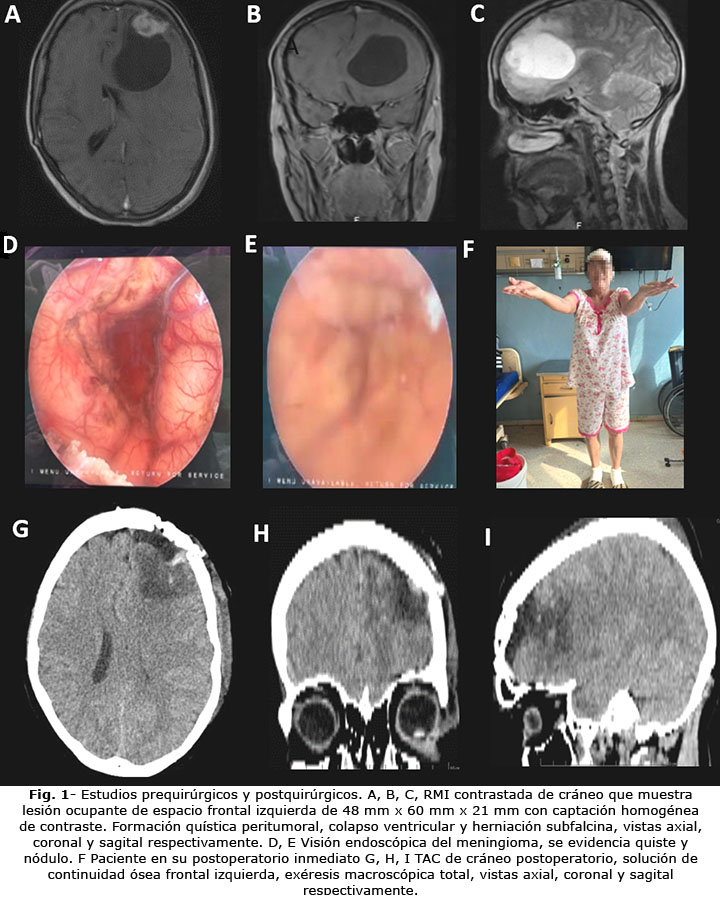

RMI de cráneo simple y contrastada: lesión ocupante de espacio frontal izquierda de 48 mm x 60 mm x 21 mm, hipercaptante de contraste, con un quiste peritumoral lateral, colapso del sistema ventricular ipsilateral y herniación subfalcina (Fig . 1).

El diagnóstico radiológico reveló metástasis cerebral. Se optó por realizar una craneotomía frontal con apoyo endoscópico y exéresis de la lesión. Se aspiraron 25 mL de líquido xantocrómico del quiste, con exéresis del nódulo adyacente a la duramadre no infiltrada, de color grisáceo, fácil disección y poco vascularizado. Se practicó una exéresis macroscópica total, bajo la sospecha diagnóstica de metástasis cerebral, aunque las paredes del quiste no estaban definidas con un plano de clivaje efectivo con el tejido cerebral. El estudio anatomopatológico informó meningioma meningotelial quístico (Fig. 2).